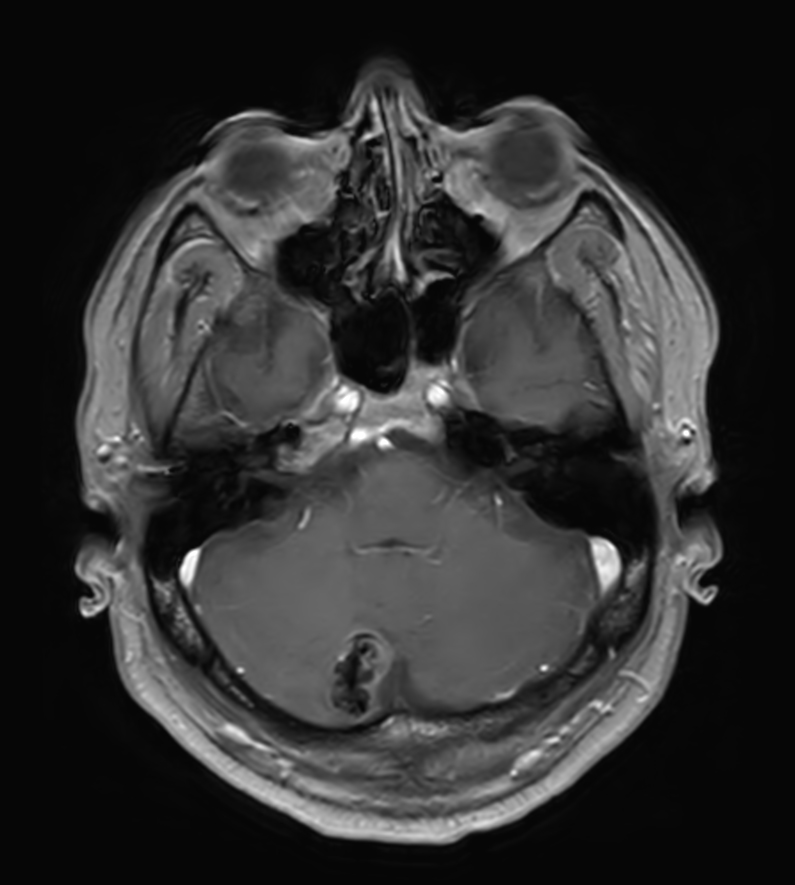

Patient with a lesion in the cerebellum. The ExamCard includes Compressed SENSE to accelerate the entire exam and techniques for motion reduced imaging (MultiVane XD), 3D imaging to acquire high resolution data in multiple directions, 3D susceptibility weighted imaging (SWIp), angiography sequences (Time-of-Flight and Contrast-Enhanced MRA with both arterial and venous phases), DTI with MultiBand SENSE to acquire a high number of diffusion directions in a short scan time and EPIC Brain to bring down any residual distortion.

T1w FFE Compressed SENSE

T1w FFE post-gado Compressed SENSE